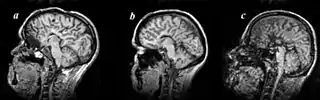

Colpocephaly is characterized by disproportionately large occipital horns of the lateral ventricles (also frontal and temporal ventricles in some cases). MRI and CT scans of patients demonstrate abnormally thick gray matter with thin poorly myelinated white matter. This happens as a result of partial or complete absence of the corpus callosum. Corpus callosum is the band of white matter connecting the two cerebral hemispheres. The corpus callosum plays an extremely important role in interhemispheric communication, thus lack of or absence of these neural fibers results in a number of disabilities.[12]

The lemon sign on CT scans of patients refers to the shape of the fetal skull when the frontal bones lose their normal convex contour and appear flattened or inwardly scalloped. This gives the skull a shape similar to that of a lemon. The sign is seen on transverse sonograms of the fetal cranium obtained at the level of the ventricles. A special case is found in literature where lissencephaly, colpocephaly, and septal agenesis are all present together. The CT scans of the patient shows the ventricular system having a unique appearance of a crown of a king. This is referred to as the 'CROWN SIGN'.[8]

Image indicates colpocephaly with septal agenesis

Corpus callosum

After birth, MR imaging can be done to look for cephalic abnormalities. This is the most commonly used method for diagnosing colpocephaly. Physicians look for abnormally large occipital horns of the lateral ventricles and diminished thickness of white matter.[12] Spinal tapping is not a preferred method for diagnosis because newborn babies with colpocephaly or hydrocephaly have open fontanelles which makes it difficult to collect CSF. Also, colpocephaly is not associated with increased pressure.[13]